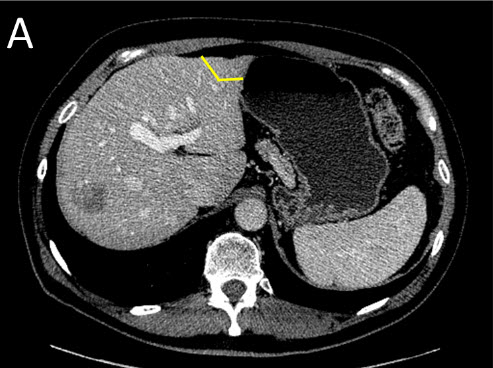

![]() |

| (A) Staged Liver Resection: First Surgery (Stage I) - the tumors on the future remnant liver are treated first by resection or ablation |